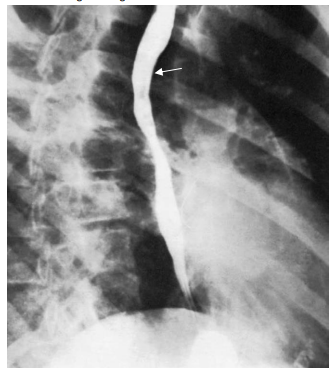

Observe a imagem a seguir.

A seta indica